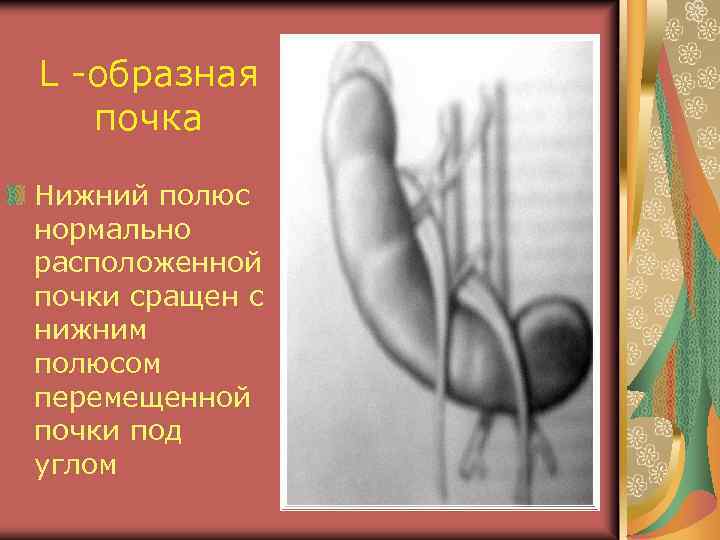

L -образная почка Нижний полюс нормально расположенной почки сращен с нижним полюсом перемещенной почки под углом

L -образная почка 1. Правая почка при продольном сканировании 2. Левая почка при поперечном сканировании по средней линии

L- образная почка Левая почка перемещена вправо Сращение нижнего полюса правой почки и нижнемедиальной поверхности левой почки